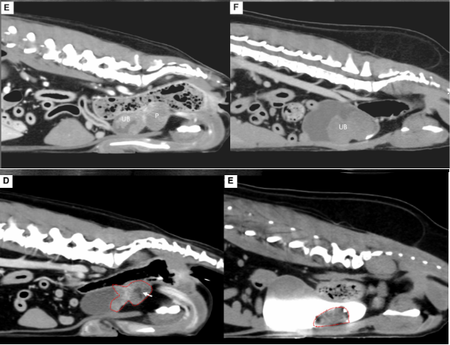

■ 급성 대동맥 혈전증 환자에 ‘Stent-Retriever 혈전제거술’ 적용

두 번째 논문은 급성 대동맥 혈전증으로 후지 마비가 발생한 개에서 stent-retriever를 이용해 혈전을 제거하고 정상 보행을 회복한 증례로 'Journal of American Animal Hospital Association(SCI)'에 게재됐다.

인의 신경계 인터벤션 시술에서 사용되는 Stent-retriever(Solitaire)를 수의학에 적용한 최초의 사례로, 혈전 제거 직후 양측 대퇴동맥의 혈류가 회복되었고, 환자는 시술 후 빠르게 자발 움직임을 보였으며, 8일 차에는 정상 보행을 회복했다. 기존의 외과적 혈전제거술이나 흡인식 혈전제거술보다 짧은 시간 내에 높은 치료 효과를 보였다는 점에서 임상적 가치가 크다.